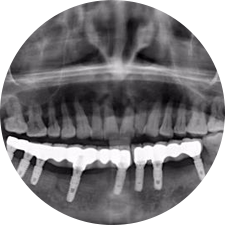

口腔種植是將人工牙根通過手術(shù)植入牙骨內(nèi),獲得牙槽骨牢固的支持,通過特殊的裝置和方式連接牙修復(fù)體,獲得與天然牙功能、結(jié)構(gòu)以及美觀相似的效果。

河北惟德口腔醫(yī)院擁有國內(nèi)豐富的半口/全口、即刻負重種植案例,十八年案例跟蹤分析,總結(jié)梳理出的各種不同類型的種植案例,Nobel種植體系針對半口/全口缺牙患者,通過4-8顆種植體可快速達到牙齒重建,不僅植入種植體較少,節(jié)省費用,手術(shù)時間更短。

術(shù)前患者CBCT口掃1:1三維重建,模擬手術(shù)過程及預(yù)測術(shù)后治療效果,確定每顆植體植入的適合的種植位點、深度及角度,有效避免損傷頜骨重要解剖結(jié)構(gòu),提高手術(shù)準確度與安全性。

Noble口腔種植體系基本不受年齡限制,適用于缺牙修復(fù),也適用于牙槽骨萎縮、骨質(zhì)疏松、高血壓、糖尿病、超高齡的患者,即種即用,只需少量微小種植體,便可輕松微痛快速重建全口咬合,特殊力學(xué)設(shè)計,針對許多年紀較大,骨質(zhì)條件差,身體耐受力差的缺牙老人也能完成“即種即用”,受到廣泛好評。

惟德口腔種植體系是以患者感受為中心,取代傳統(tǒng)種植牙手術(shù)需要翻瓣、打孔、縫合,術(shù)前、術(shù)中、術(shù)后的繁復(fù)流程,采用3D導(dǎo)航微創(chuàng)準確種植技術(shù),通過數(shù)字化CAD/CAM掃描技術(shù)獲得缺牙患者口腔數(shù)據(jù),以數(shù)據(jù)為基礎(chǔ)重建口腔模型進行模擬種植。

術(shù)前將患者口內(nèi)的CBCT數(shù)據(jù)及咬合關(guān)系上傳到計算機中,建立1:1三維重建,模擬手術(shù)過程及預(yù)測術(shù)后治療效果,找出較佳種植位點、深度及角度,獲取實際種植體在頜骨內(nèi)的具體三維位置,有效避免損傷頜骨重要解剖結(jié)構(gòu),大大降低手術(shù)風(fēng)險,提升種植成功率。